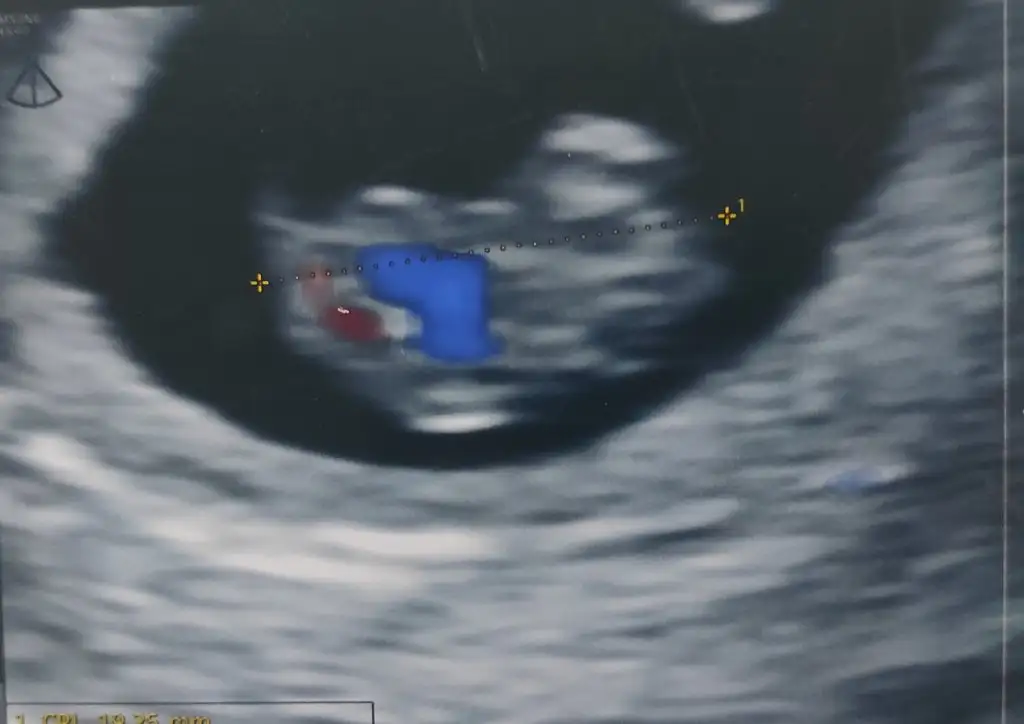

Merhaba 6+5 çift yumurta ikizleri (iki ultrasonda ayrı )vajinal muayane 3. Fotoda iki kese görünüyor